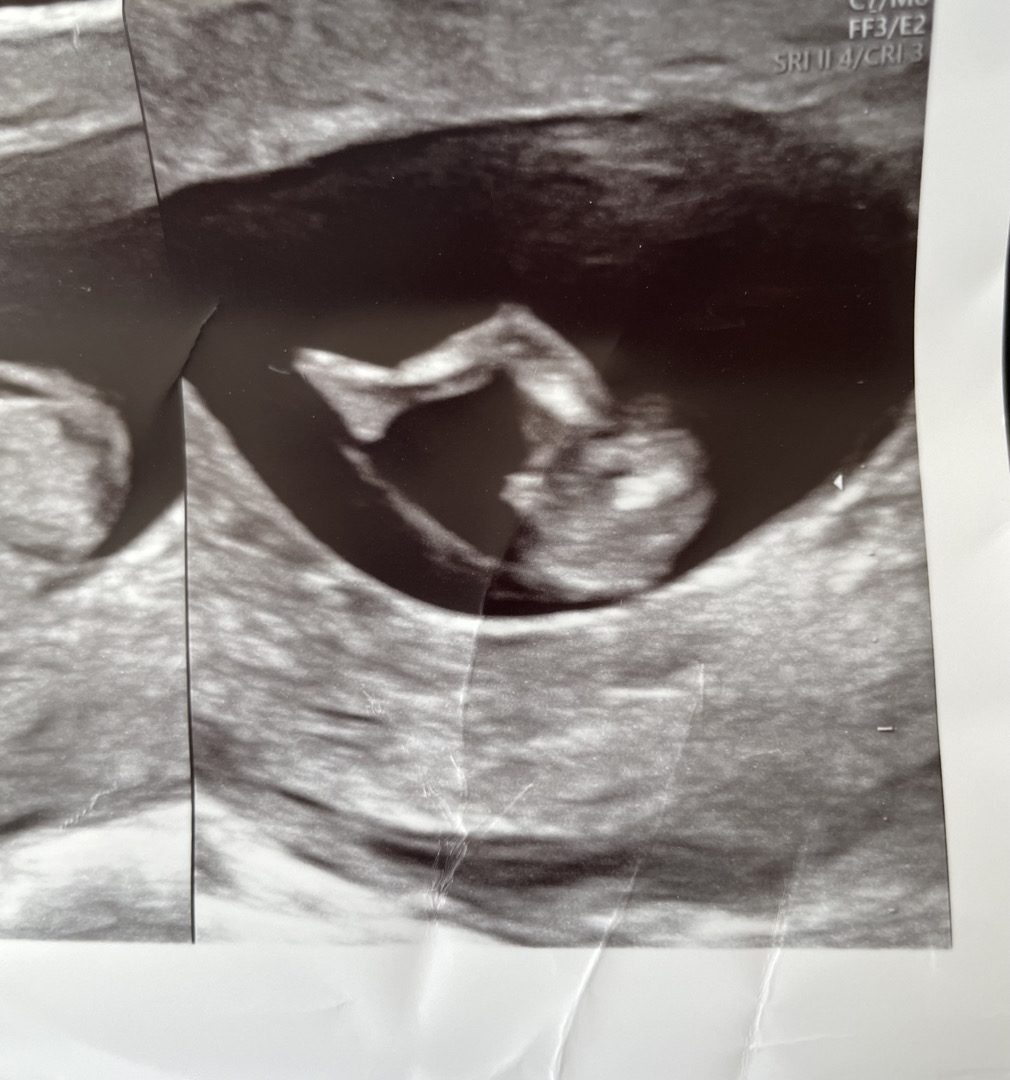

11주차 초음파 참견 부탁드려요~

다리 사이가 이런거면 아들일까요~? 초음파 비슷하게 나왔는데 성별 벌써 아시는 분 있으신지 궁금하네요!!

여기서 더나오거나 없어지거나라서 아직모르지싶어요!

아들같아용 저희애도 촘파로 나와있어요 ㅋㅋ